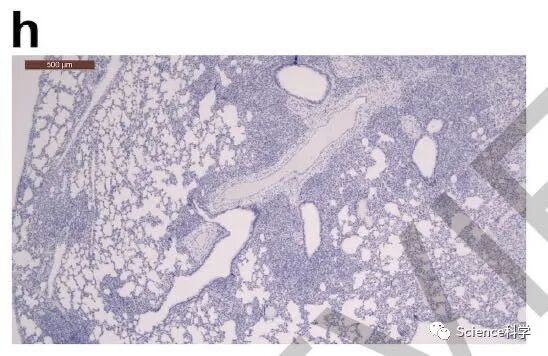

接种病毒后5天在支气管周围区域检测到CD3阳性T淋巴细胞,这可能有助于快速清除受感染的细胞,如下图所示: